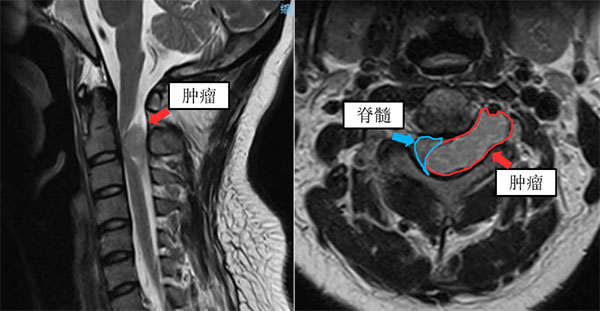

到了当地的医院进行检查,发现她在高位颈椎平面的椎管内有一个哑铃型肿瘤,一侧把脊髓压成了月牙形,另一侧还把椎动脉推到了前方。磁共振清晰看到,脊髓受压的部位已出现水肿信号,意味着脊髓已被压伤。

(肿瘤磁共振图像显示严重压迫脊髓)